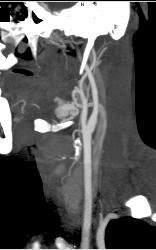

Normal Carotid Artery